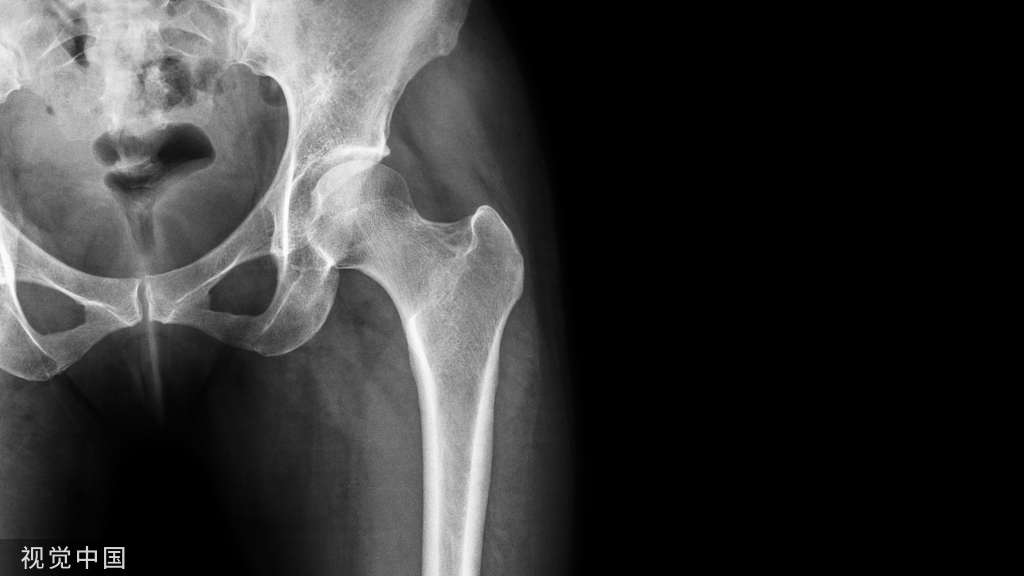

此病例引起很多口腔医生重视,因为阻碍磁共振等同于无法第一时间抢救生命!分秒必争!于是,当广大牙病患者在选择做金属牙套和全瓷牙套时,医生大多会建议应首选不影响磁共振 、不影响拍CT、不影响X射线的材料最靠谱的选择——二氧化锆全瓷牙。二氧化锆对核磁共振没有影响。

3、核磁共振检查时,非金属的氧化锆对X线无任何阻挡,核磁共振检查时都不需要拆掉假牙,省去很多麻烦。